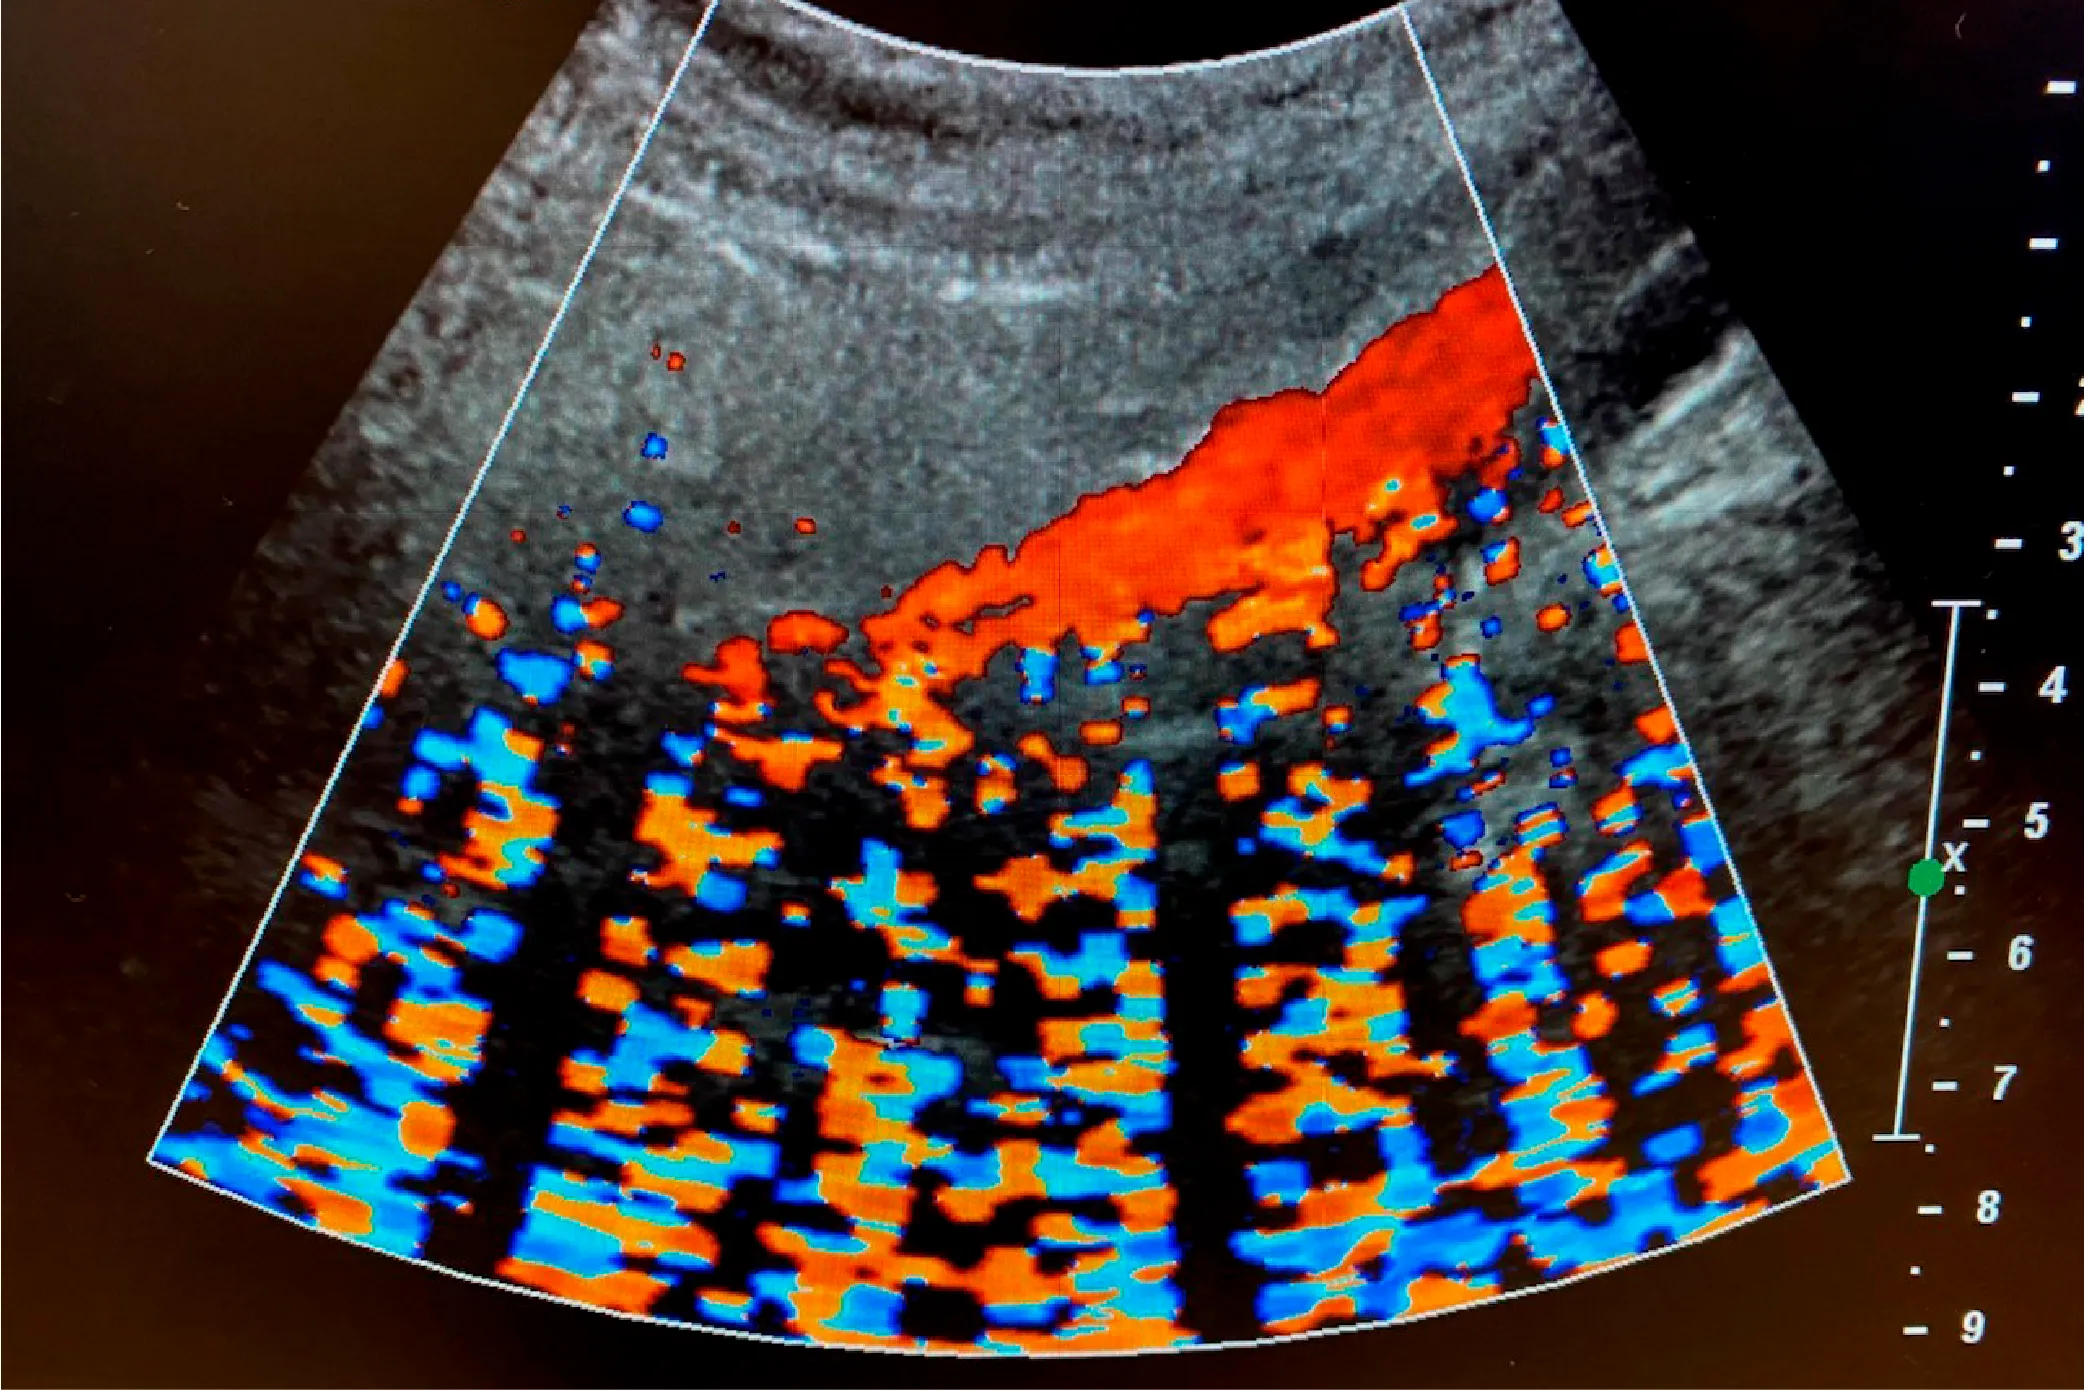

Providing detailed images of the body using technologies such as X-ray, MRI, CT scans, and ultrasound to aid in the diagnosis of various medical conditions.